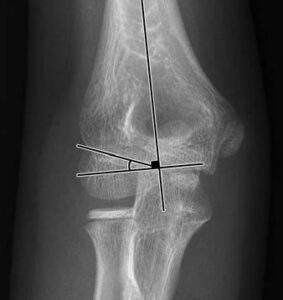

[toggle title=”Baumann açısı (Humerokapitellar açı)” state=”close”]

Lateral kondiler fizeal açı ile humerus uzun ark arasında kalan açıdır.

Normali 10-20°dir. Karşı eklemle karşılaştırılmalı, aralarındaki fark >5° olmamalıdır.

Distal humerus kırıklarının değerlendirilmesi yanı sıra kırıkta yapılan redüksiyon başarısının değerlendirilmesinde de kullanılır.